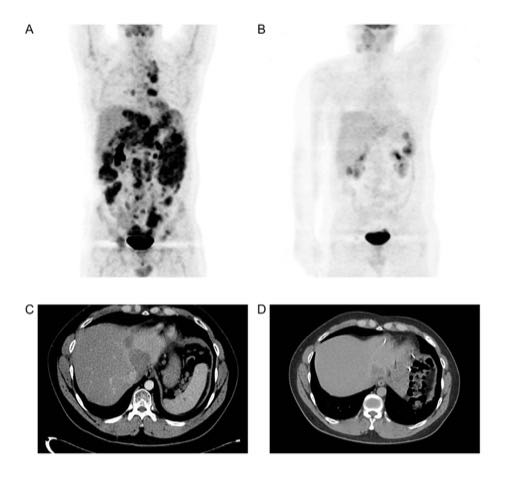

其中一位患者的故事尤为鼓舞人心。该患者于2014年确诊晚期卵巢癌,历经手术、化疗,病情仍不断进展。2019年入组NK细胞治疗临床研究时,体内已有多个转移病灶。经过13次NK细胞治疗,截至2020年9月,患者已存活超过40个月,且影像学检查显示病灶明显缩小甚至消失。